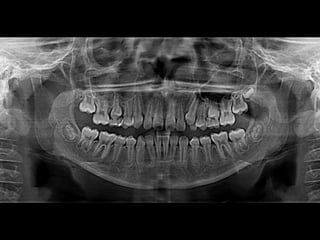

RADIOGRAFÍAS PANORÁMICAS